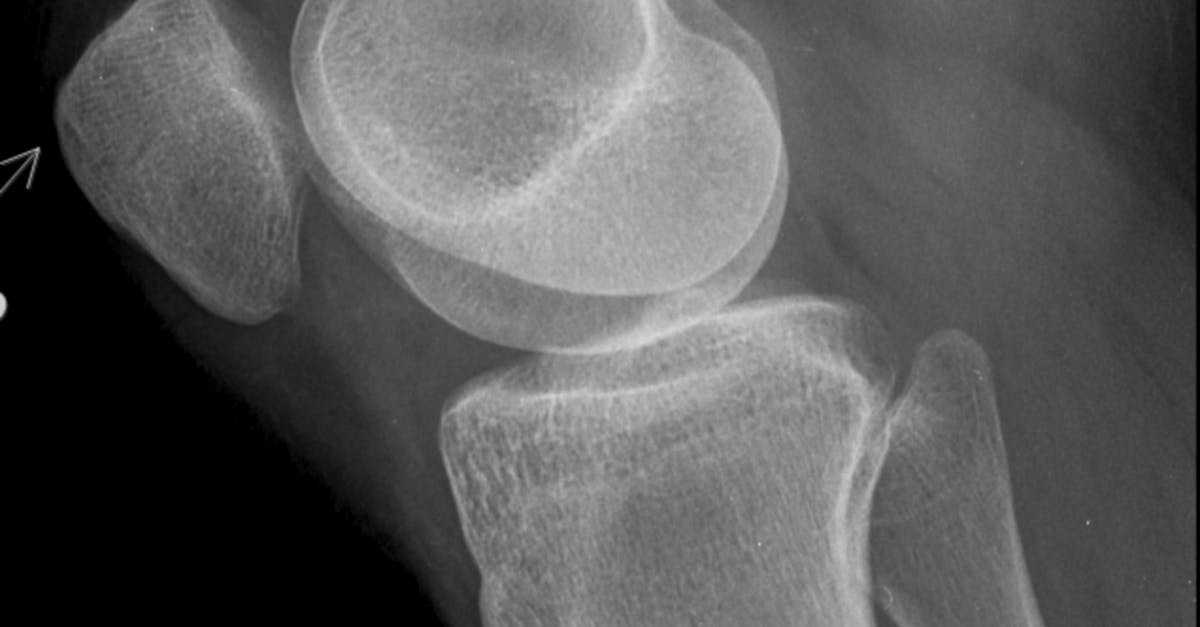

7. Joint Deformity and Structural Changes

Photo Credit: Pexels @Gayan Kavinda

Progressive joint deformity and structural changes represent some of the most visually striking and functionally significant consequences of chronic systemic inflammation affecting the wrists and ankles. The inflammatory process, when persistent and inadequately controlled, leads to destruction of articular cartilage, erosion of subchondral bone, and damage to supporting ligamentous structures, ultimately resulting in permanent alterations to joint architecture. In the wrist, common deformities include ulnar deviation of the fingers, radial deviation of the wrist itself, and the development of a characteristic "zigzag" deformity as the normal alignment relationships become disrupted. The inflammatory process can also lead to carpal collapse, where the normal height and architecture of the wrist are lost due to cartilage destruction and bone erosion. At the ankle, chronic inflammation may result in valgus or varus deformities, where the foot tilts inward or outward relative to the leg, and the development of prominent bony prominences as the normal joint surfaces become irregular. These structural changes occur gradually over time, often beginning with subtle alterations in joint alignment that may be barely noticeable in the early stages but progressively worsening as the inflammatory process continues. The deformities not only create cosmetic concerns but also significantly impact function, leading to reduced range of motion, altered biomechanics, and compensatory changes in adjacent joints. Early recognition and aggressive treatment of systemic inflammation are crucial for preventing or minimizing these irreversible structural changes.